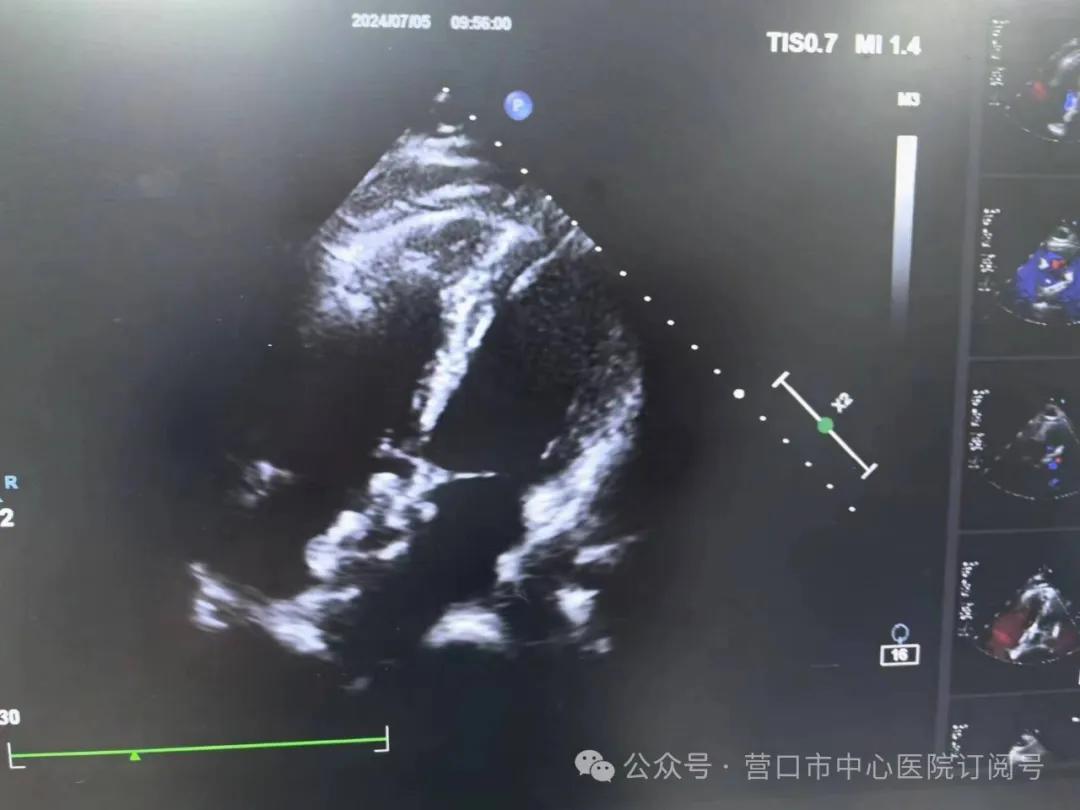

中年女患,因“胸闷、气短5年,加重半个月”就诊,完善心脏超声确诊先天性心脏病房间隔缺损,缺损较大,直径达18mm,并且已经导致右心显著增大(图1)。经过多学科会诊,并与超声科主任反复沟通,充分术前讨论及评估,考虑患者可以实施介入封堵治疗,无需外科开胸手术。在周密的术前准备后,为患者实施房间隔缺损介入封堵治疗。整个团队密切配合、精准操作,手术用时仅约半小时,就将缺损部位完美堵住。术后24小时复查心脏彩超证实完全封堵,无残余漏,且未影响房室瓣活动及上、下腔静脉回流,右房及右室均明显缩小,右房从41*47mm降至35*45mm,右室大小从37mm降至17mm,效果显著(图2、3)。患者术后第1天离床活动,术后3天出院,恢复良好。

图1 剑下四腔心切面,可见房水平左向右分流